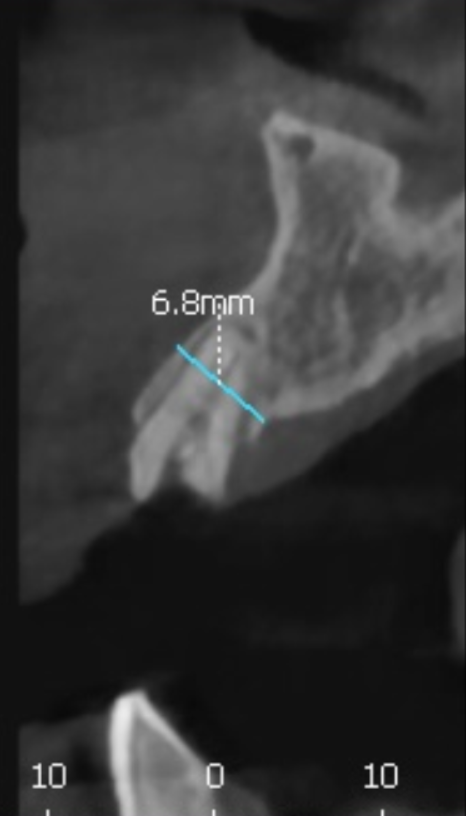

저희는 환자분들의 정확한 상태를 파악하기 위해

3D CT를 아주 꼼꼼하게 돌려보며 진단해요.

실제로 뼈이식이 꼭 필요한 부위인지,

아니면 남아있는 뼈만으로도 충분한지를

화면을 함께 보며 상세히 설명해 드립니다.

이번 환자분의 경우에도 CT를 분석해 보니

다행히 뼈의 폭이 5mm~7mm 정도로

충분히 두꺼웠습니다.

뼈의 폭이 충분하다면

굳이 뼈이식을 할 필요가 없습니다.^^